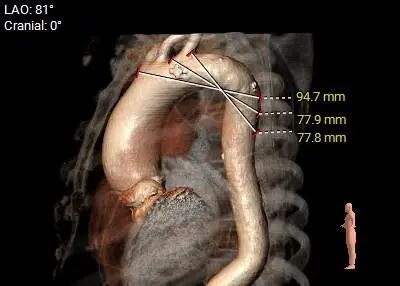

瓦氏窦内径尚可,窦管交界内径尚可,升主动脉扩张,心室腔内径偏大,心室壁厚度尚可

主动脉瓣环水平夹角71度,严重横位心,主动脉弓宽度、角度尚可,弓部存在散在钙化

外周血管及主动脉弓解剖: